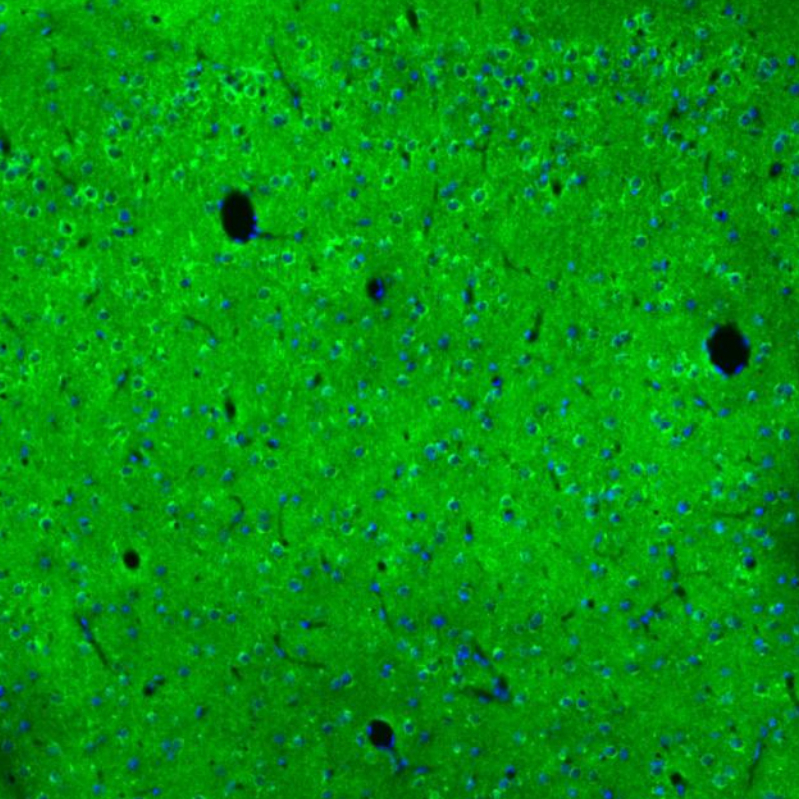

Immunohistochemical staining of human cerebral cortex shows strong granular cytoplasmic positivity in neurons and neuropil.